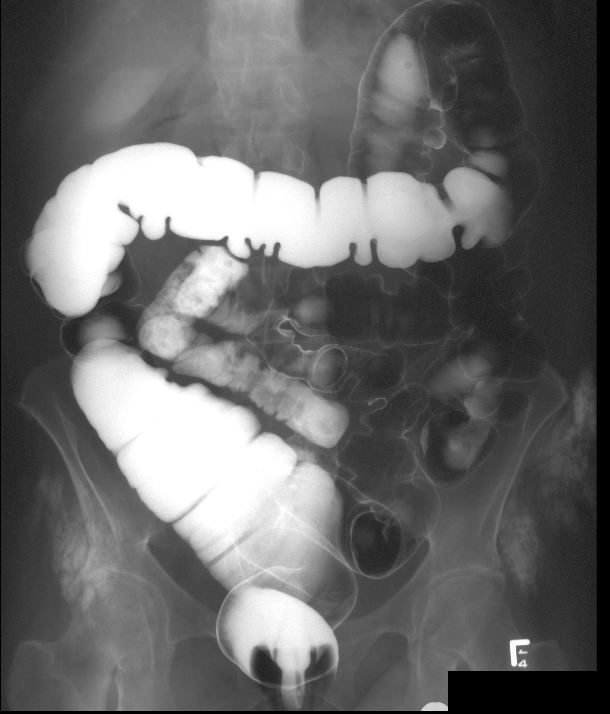

GI manifestations of scleroderma

Pseudosacculations

seen in scleroderma